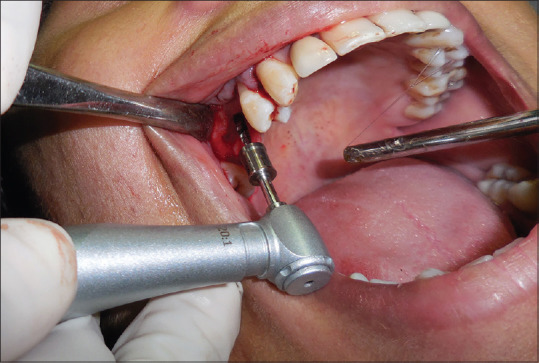

Drilling technique can significantly affect osseointegration by influencing the integrity of the osteotomy site, the bone-to-implant contact, and the mechanical properties of the surrounding bone, such as density and quality.